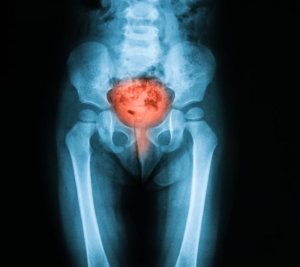

Всередину його приймають у вигляді таблеток при захворюваннях сечостатевої системи:

• гострі та хронічні цистити

• уретрити будь-якого характеру

• хронічний нефрит

Лікування циститу Фурагіном

Хороші показники дає антимікробний препарат Фурагін при лікуванні циститу — поширеного захворювання сечового міхура. Тому він часто призначається урологами при цій хворобі.

Лікування циститу ускладнюється тим, що інфекція викликає його, ховається в складках ненаполненного сечового міхура. Наповнення ж запалення сечового міхура супроводжується болісними позивами до сечовипускання і людина спорожняє його, не даючи стінок повністю розправитися. Виходить порочне коло. Фурагін більшою своєю частиною концентрується саме в сечовому міхурі і справляється зі збудниками хвороби в ньому. Якщо врахувати той факт, що патогенна мікрофлора легко мутує, а тому набуває стійкість до більшості антибіотиків, стають очевидними переваги Фурагіну.